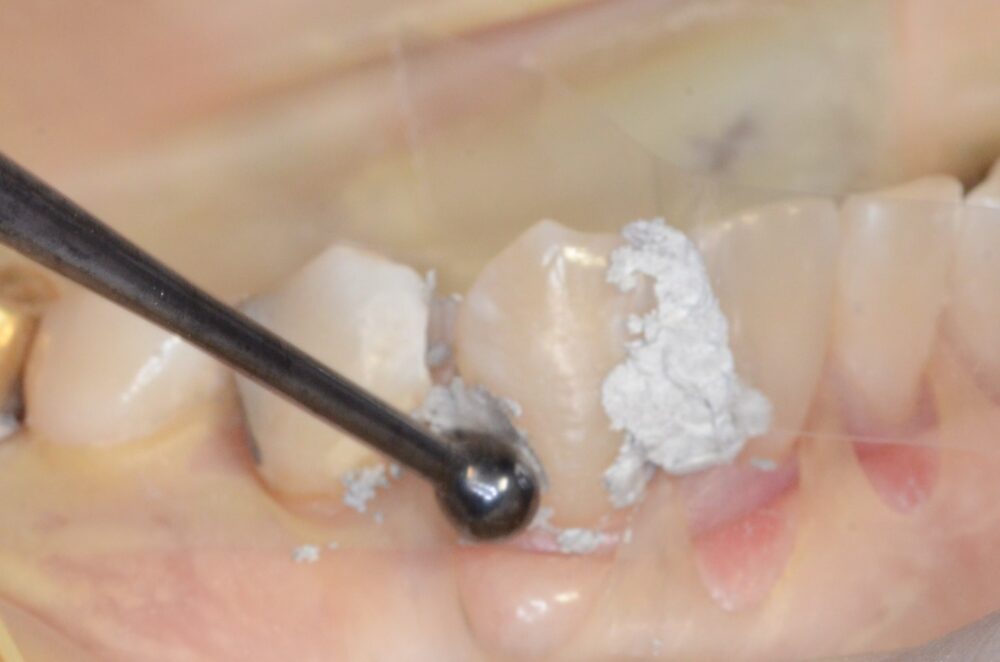

例えば、虫歯がひどく単に充填するだけでは歯の強度を元に戻すのが難しい歯の場合ピンを使います。

下の写真のようにピンを打って支えを作った歯にアマルガムを充填し、そのアマルガムを残したまま、ゴールド修復を行い、歯を被せることによって、強度を取り戻した歯にすることができます。

これらの治療は神経を刺激しない位置にチタン製でできたピンを打ち込まねばならず非常に神経を使う仕事です。